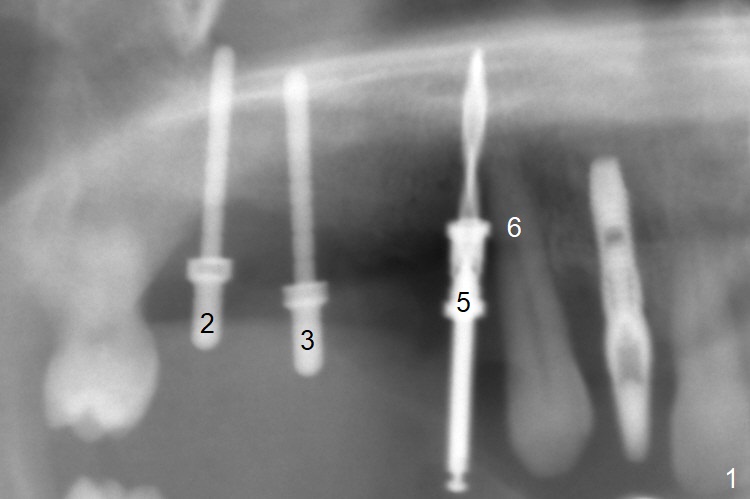

After extraction, the depths of initial osteotomy at #2, 3 and 5 are 13, 11.5 and 10 mm, respectively (Fig.1). Following adjustment of trajectory, a 3.8x13 mm UF implant is placed at #5 (Fig.2) with insertion of a 4.5x2 mm mill abutment as well as mineralized cortical/cancellous allograft (Vanilla, *). The mill abutment is chosen because the margin of a 5.5x7(5) mm cemented abutment is severely subgingival (Fig.4 at #3; ^ gingival margin). By the same token, a 4.5x3 mm mill abutment is placed at #2. In fact all of the 3 implants are placed 2-3 mm out of the bone (Fig.5). To prevent periimplantitis, abundant allograft is placed around the implants/abutments (Fig.2,4 *). Nearly 2 months postop, the mill abutment at #2 is adjusted for its height, while a 5.5x2.5 mm mill abutment is placed at #3 (Fig.6). To regain the buccal gingiva, the buccal margin of the provisional is shortened (Fig.6,7). Two weeks later, the gingival regrowth is not obvious (Fig.8 (nearly 3 months postop)). Local poor oral hygiene remains. A provisional FPD is fabricated. If his occlusion is normal for another 2 weeks, impression will be taken for upper (or UL) permanent restoration.